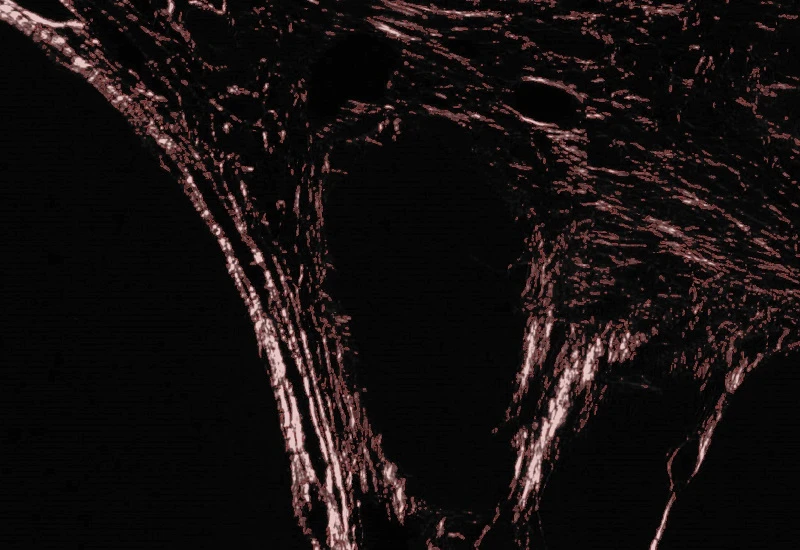

Sirius Red Polarized

Quantify collagen type I (red) and type III (green) fibers in Sirius Red–stained polarized images, measuring region area and the area of red, green, and overlapping (double-positive) fibers.

The Sirius Red Polarized App allows for quantification of collagen type I and type III based on Sirius Red Staining imaged with polarized light. It outputs the region area (µm2), the area of collagen type I = red fibres (µm2), collagen type III = green fibres (µm2) and overlapping fibres (µm2).

Image courtesy of Dr. Mortiz Uhlig, University Hospital RWTH Aachen

Detection of collagen type I